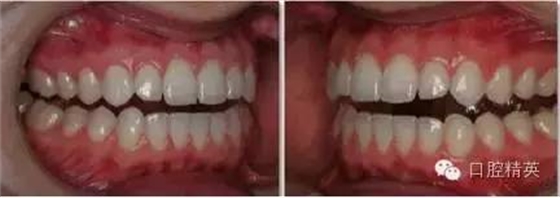

上下颌牙列照

正面观

1:2 (1:3)放大倍率

需要使用拉钩

• 上下颌牙应轻微张开使得切端清晰可见。这样有利于切缘平面喝切缘楔状隙的分析。

•露出尽量多的牙龈。对称放置拉钩,以免造成倾斜的假象。将拉钩向远离牙齿的方向拉。

•减少相片中嘴唇及拉钩的影像。

•待治疗的牙齿及周缘组织应能清晰可见。牙龈高度及轮廓应不被遮盖。

•脸部中线应作为照片纵向中线。对其人中可能有些帮助,但是拉钩有时会造成软组织的偏斜。

•相片的水平中线为上牙切缘平面,垂直于纵向中线。

•相机应位于拍摄对象正前方,并与其成90°角。避免倾斜相机,或者发生垂直向角度偏斜的问题(俯拍或仰拍)。

•在中切牙及侧切牙处对焦。选取适当的景深(通过高F值获得)使得尽可能多的牙齿在焦距内。

•舌头应往后缩,以免遮挡牙面。

•使用1:2 (1:3)放大倍率,使得上下颌牙弓均位于焦距内。